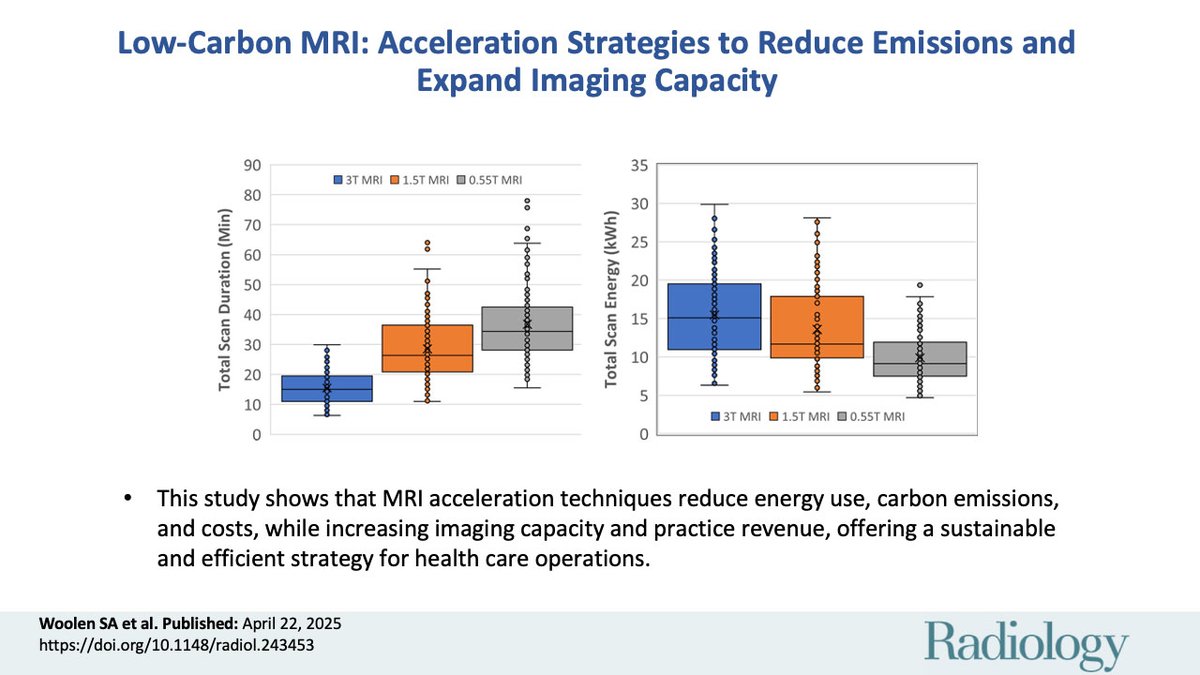

Can faster MRI be greener too? 🌍🧠 This study by Sean Woolen MD MS Kate Hanneman Susie Huang Azadeh Tabari Jan Vosshenrich, MD shows how acceleration cuts energy use, emissions, and costs, while boosting capacity. A smart, sustainable win! #LowCarbonMRI #Radiology pubs.rsna.org/doi/10.1148/ra…

Woolen et al measured the energy expenditures during specific MRI protocols on different field-strength magnets. Read on to see the results! #RadGoesGreen UCSF Imaging Sean Woolen MD MS Kate Hanneman Susie Huang Azadeh Tabari Jan Vosshenrich, MD Christopher Hess bit.ly/4jGof2n